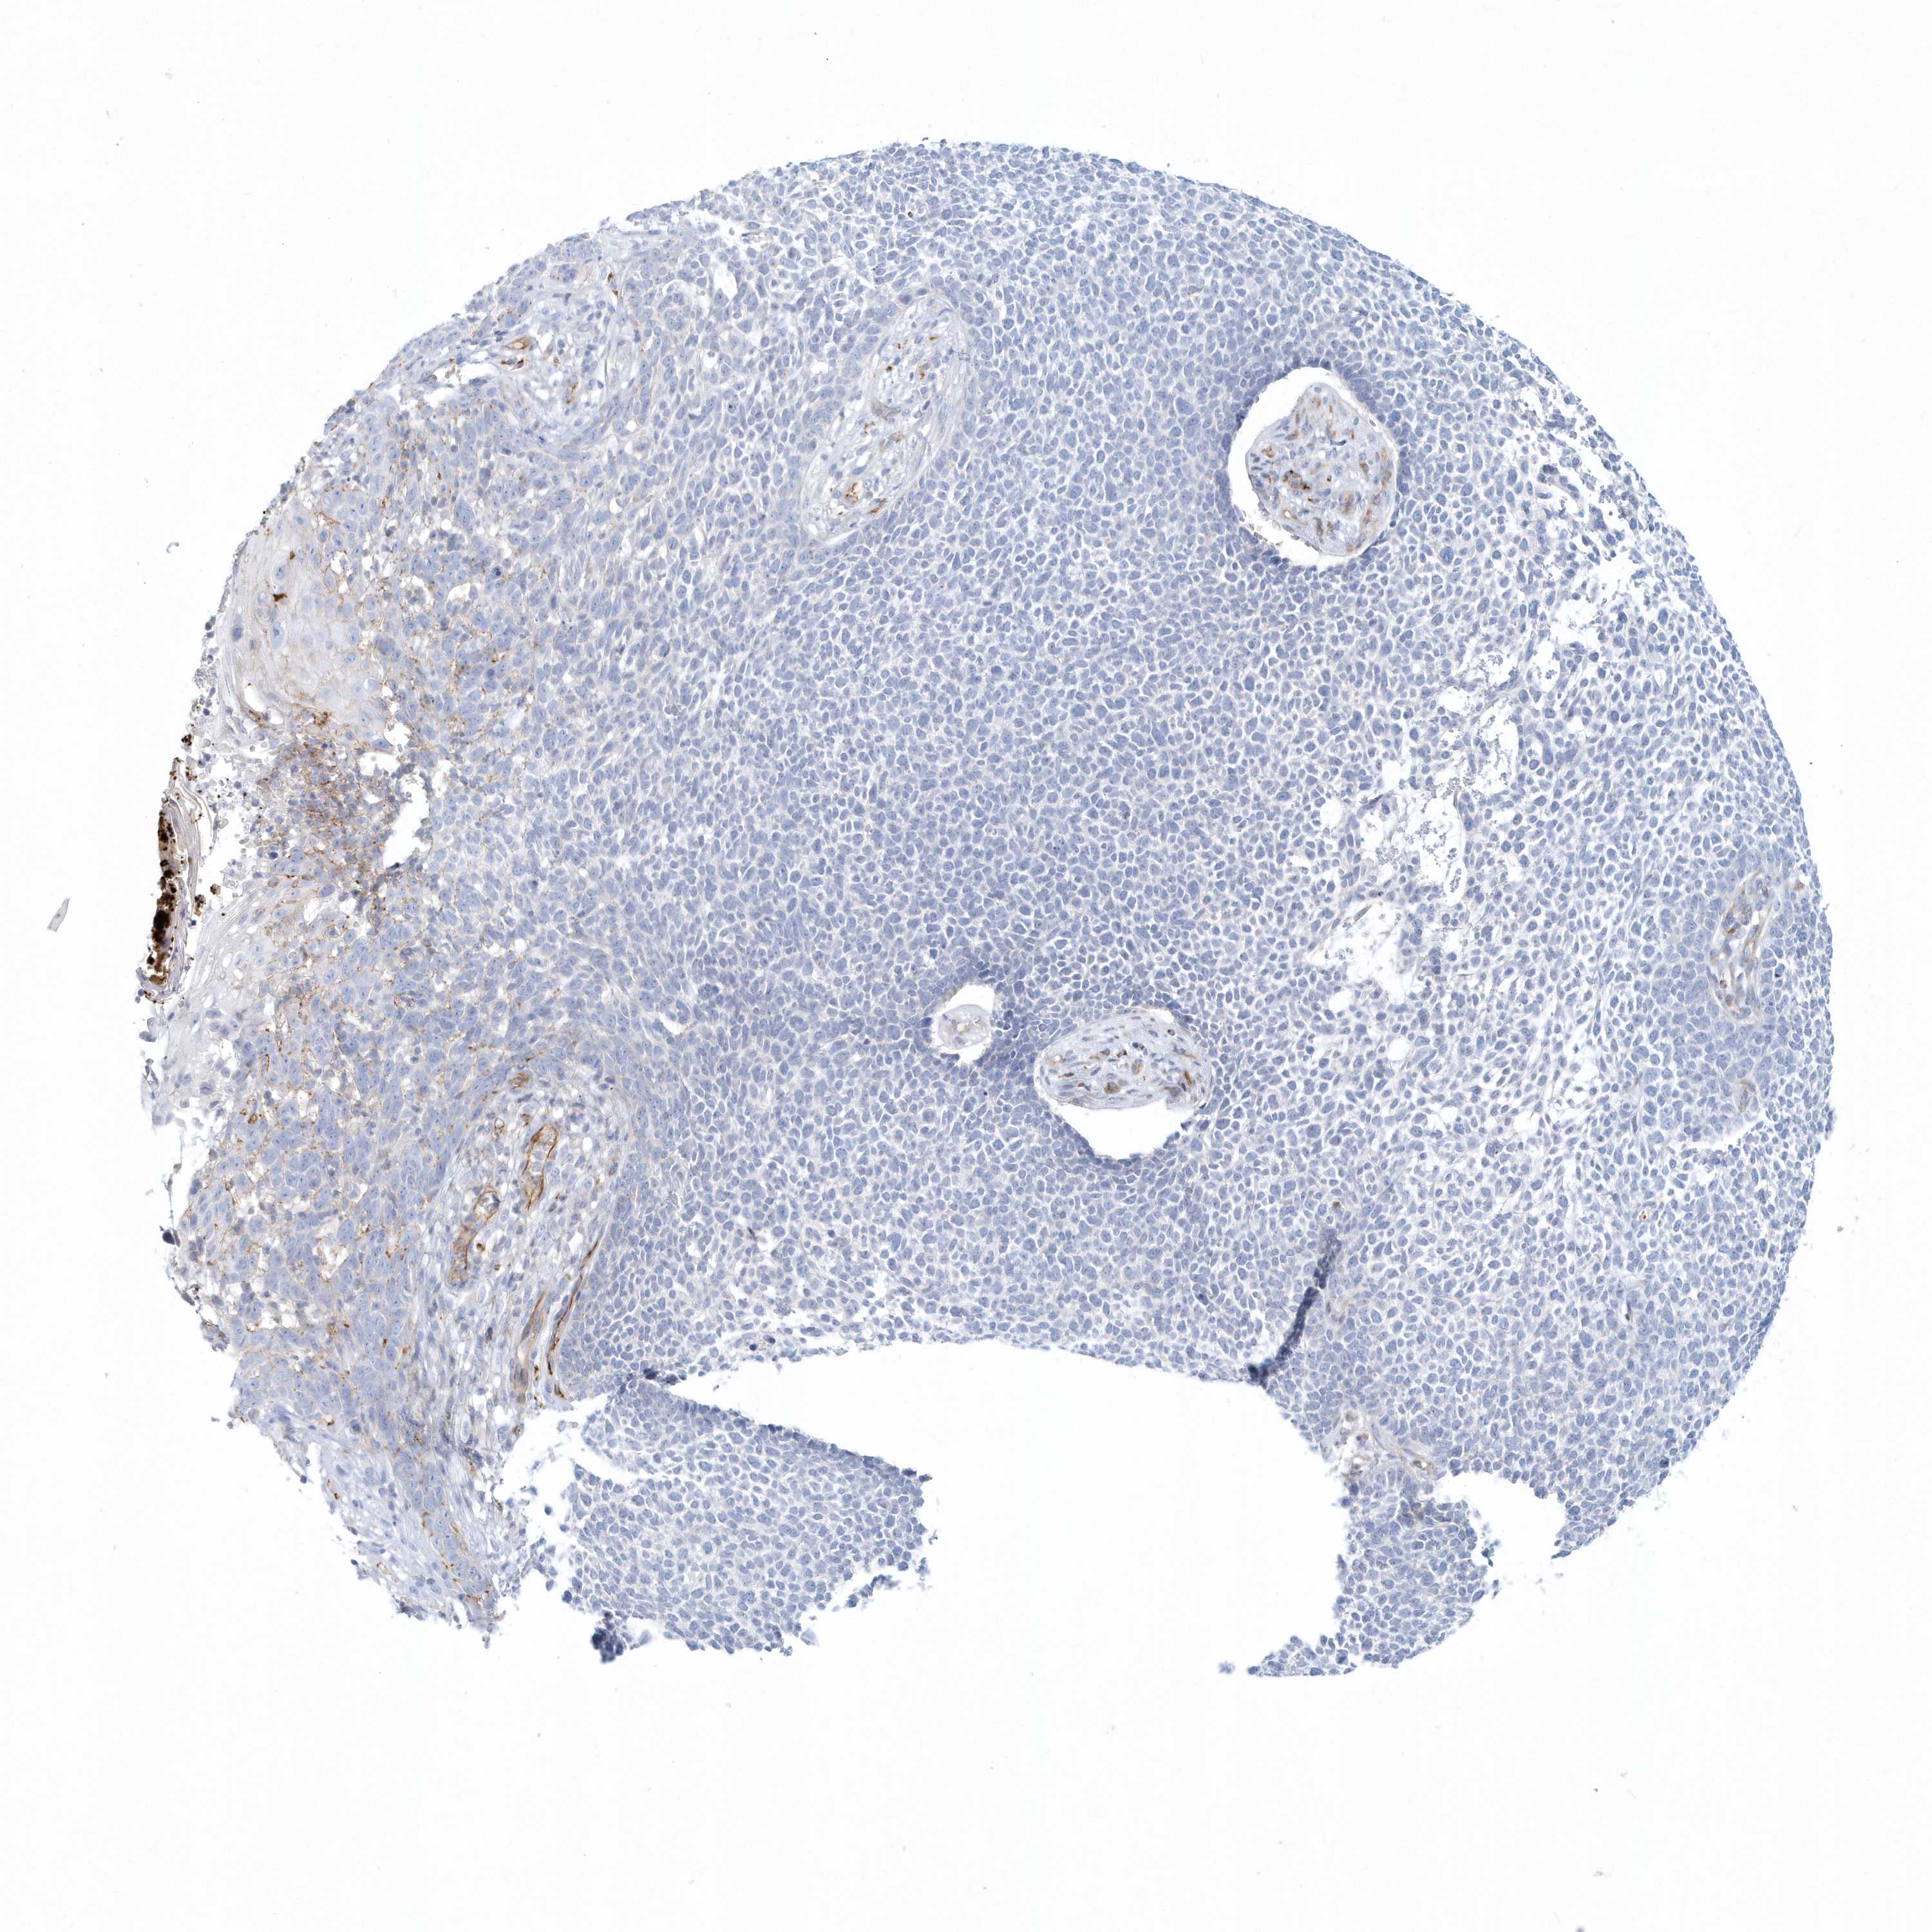

Basal cell and squamous cell cancer

SKIN CANCER - Protein expressioni

A mouse-over function shows sample information and annotation data. Click on an image to view it in a full screen mode. Samples can be filtered based on level of antibody staining by selecting one or several of the following categories: high, medium, low and not detected. The assay and annotation is described here.

Antibody stainingi

Antibody staining in the annotated cell types in the current human tissue is reported as not detected, low, medium, or high, based on conventional immunohistochemistry profiling in selected tissues. This score is based on the combination of the staining intensity and fraction of stained cells.

Each image is clickable and will lead to virtual microscopy that enables deeper exploration of all samples and also displays staining intensity scores, fraction scores and subcellular localization as well as patient and tissue information for each sample.

Antibody HPA036805

Antibody HPA036806

Staining

Not detected

Negative

None

Basal cell carcinoma